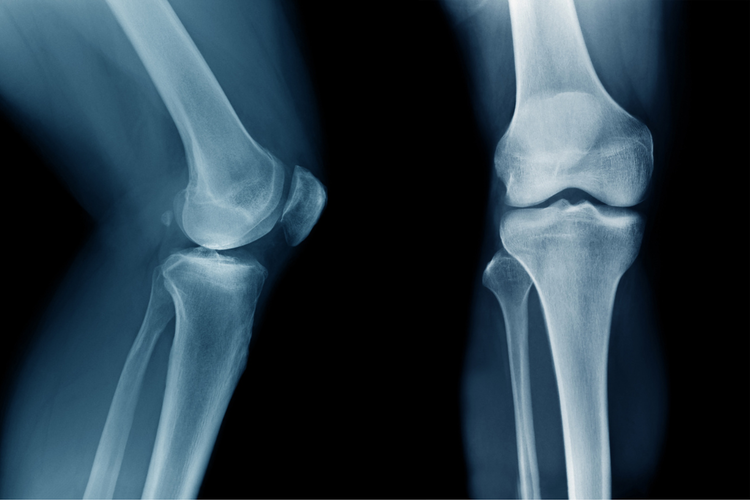

Knee X-ray illustrating imaging used to assess bone alignment and diagnose ski knee injuries.

Assessment steps may include:

• Reviewing the mechanism of injury, such as twisting, landing awkwardly, or catching an edge.

• Evaluating symptoms, including swelling, instability, or difficulty bending or straightening the knee.

• Performing clinical tests to assess ligament stability and identify possible meniscus involvement.

Imaging may be useful when further clarification is needed:

• X-rays can help exclude fractures or assess bone alignment.

• MRI provides detailed evaluation of ligaments, cartilage, and other soft tissues.